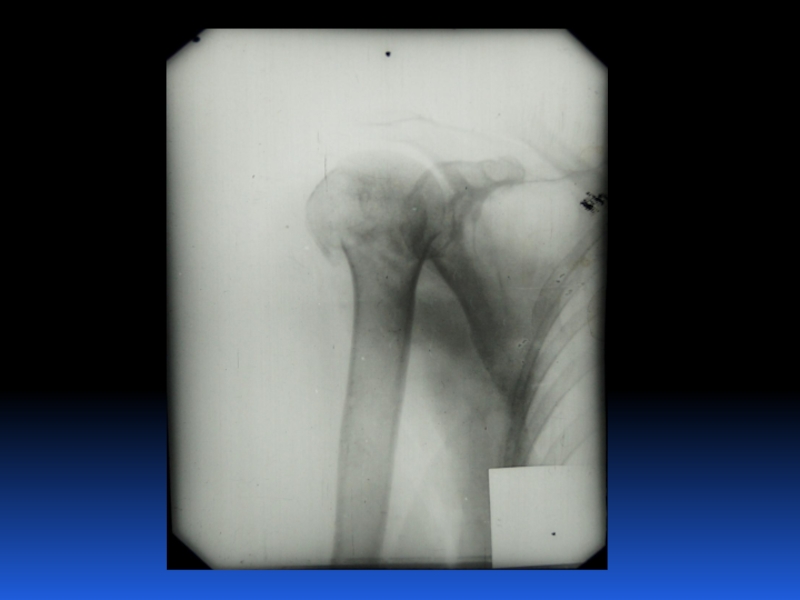

Остеопороз – это системное заболевание скелета, характеризующееся снижением костной массы и нарушением микроархитектоники костной ткани, с последующим увеличением хрупкости костей, со склонностью к патологическим переломам.

Слайд 2 Остеопороз – это системное заболевание скелета, характеризующееся снижением костной

массы и нарушением микроархитектоники костной ткани, с последующим увеличением хрупкости

костей, со склонностью к патологическим переломам.